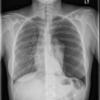

3 tension